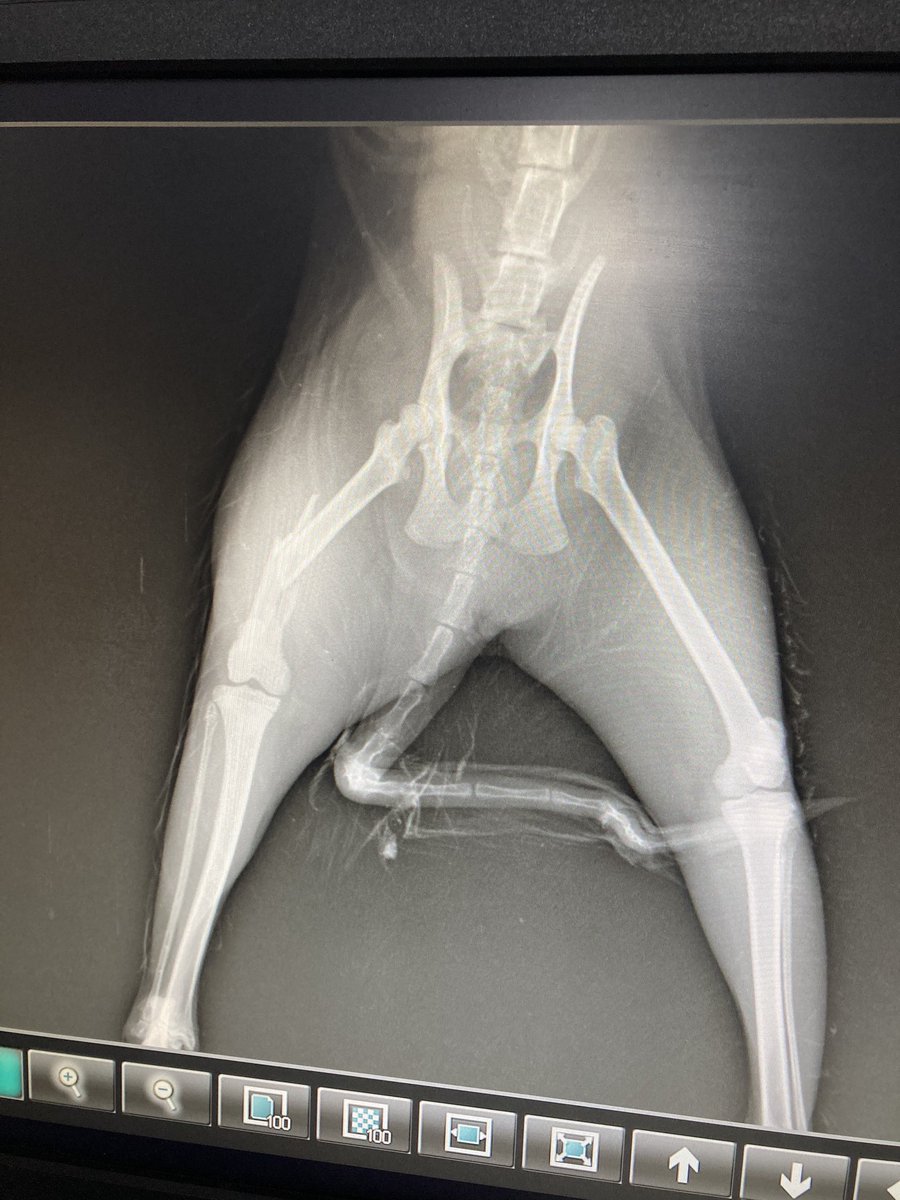

Took her to our dog’s regular vet (God bless you Dr Nandini from My Pet’s Choice Clinic, HSR layout) and got an x-ray done. Fracture of the mid thigh bone! 😢